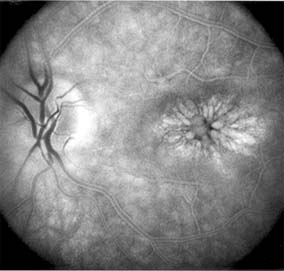

CENTRAL SEROUS CHORIORETINOPATHY

Central serous chorioretinopathy is characterized by serous detachment of the sensory retina as a consequence of focal leakage of fluid from the choriocapillaris through a defect in the retinal pigment epithelium (Figures 10-2 and 10-3). This disease typically affects young to middle-aged men and may be related to life stress events. Most patients present with the sudden onset of blurred vision, micropsia, metamorphopsia, and central scotoma. Visual acuity is often only moderately decreased and may be improved to near-normal with a small hyperopic correction.

Figure 10-2

Figure 10-2: Central serous chorioretinopathy with sensory retinal detachment (arrows) extending into the fovea.

Figure 10-3

Figure 10-3: Fluorescein angiogram of central serous chorioretinopathy shows active disease with both a retinal pigment epithelial detachment (small arrows) and a sensory retinal detachment (large arrows). Two foci of inactive disease (open arrows) are also present.

The diagnosis is made by slitlamp examination of the fundus; the presence of serous detachment of the sensory retina in the absence of ocular inflammation, subretinal neovascularization, an optic pit, or a choroidal tumor is diagnostic. The retinal pigment epithelial lesion appears as a small, round or oval, yellowish-gray spot that is variable in size and may be difficult to detect without the aid of fluorescein angiography. Fluorescein dye leaking from the choriocapillaris may accumulate below the pigment epithelium or sensory retina, resulting in a variety of patterns including the well-recognized smokestack configuration.

Approximately 80% of eyes with central serous chorioretinopathy undergo spontaneous resorption of subretinal fluid and recovery of normal visual acuity within 6 months after the onset of symptoms. Despite normal acuity, however, many patients have a mild permanent visual defect, such as a decrease in color sensitivity, micropsia, or relative scotoma. Twenty to 30 percent of patients will have one or more recurrences of the disease, and complications-including subretinal neovascularization and chronic cystoid macular edema-have been described in patients with frequent and prolonged serous detachments.

The cause of central serous chorioretinopathy is unknown; there is no convincing evidence that the disease is either infectious or due to retinal pigment epithelial dystrophy. Argon laser photocoagulation directed to the active leak significantly shortens the duration of the sensory detachment and hastens the recovery of central vision, but there is no evidence that prompt photocoagulation reduces the chance of permanent loss of visual function. Although the complications of retinal laser photocoagulation are few, it is probably not advisable to recommend immediate photocoagulation treatment in all patients with central serous chorioretinopathy. The duration and location of disease, the condition of the fellow eye, and occupational visual requirements are all considerations upon which treatment decisions are based.